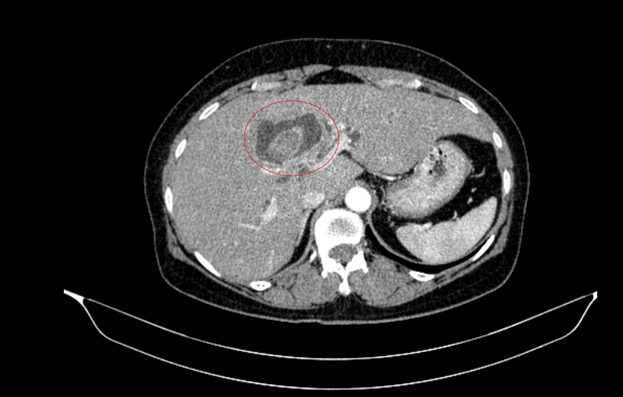

Hình ảnh sỏi đường mật tạo ổ áp xe gan - đường mật gan trái (vòng tròn màu đỏ). Giãn nhẹ đường mật trong gan hai bên. Dày thành nhẹ ngã ba đường mật trên phim chụp cắt lớp vi tính - Ảnh BVCC

Bệnh nhân nữ, 59 tuổi, nhập viện trong tình trạng vàng da, ngứa và đau vùng hạ sườn phải kéo dài. Kết quả chẩn đoán hình ảnh cho thấy tổn thương đường mật trong gan kèm sỏi và giãn đường mật.

Trong quá trình thăm khám toàn diện, nội soi tiêu hóa phát hiện thêm một khối u tại đại tràng lên. Kết quả sinh thiết xác định đây là ung thư biểu mô tuyến.

Sau hội chẩn đa chuyên khoa, các bác sĩ xác định bệnh nhân mắc đồng thời hai ung thư nguyên phát, thay vì một khối u di căn.

Cụ thể: Ung thư đại tràng phải: Giai đoạn sớm (IA), chưa di căn hạch; Ung thư đường mật trong gan: Giai đoạn tiến triển (IIIB), có xâm lấn và di căn hạch.